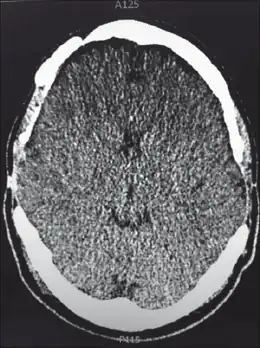

| File:MRI brain.jpg | |

| For the diagnosis, brain scans (such as MRI) should be done to rule out other potential causes | |

Neuroimaging, usually with computed tomography (CT) or magnetic resonance imaging (MRI), is used to exclude any mass lesions. In IIH these scans typically appear to be normal, although small or slit-like ventricles, dilatation and buckling[13] of the optic nerve sheaths and "empty sella sign" (flattening of the pituitary gland due to increased pressure) and enlargement of Meckel's caves may be seen.